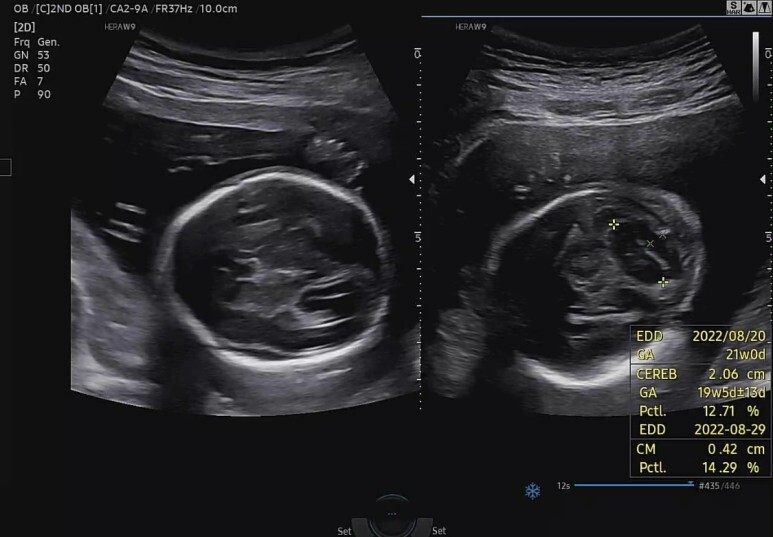

소뇌(CEREB)와 대실(CM)의 크기.